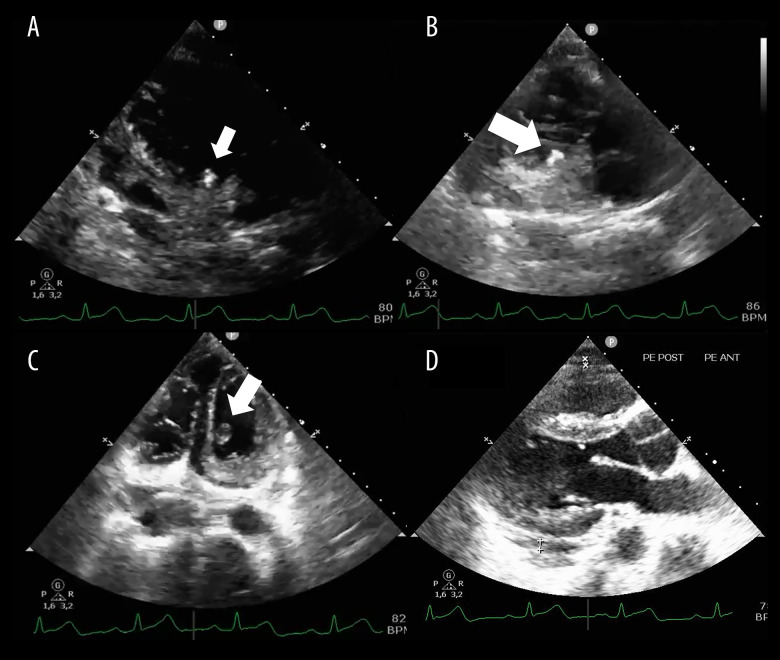

运动中经常使用的气步枪可造成复杂的、暴力性的、外伤性的心脏损伤,其发病率和死亡率都很高。与火器弹不同,气枪弹丸缺乏旋转运动,但可以达到100到230米/秒的速度。病例报告一名21岁男子在右胸气枪受伤后被转介至我院。伤后10小时出现胸痛,但血流动力学稳定。体格检查显示呼吸音减少,右半胸有压痛。胸部x线显示右侧胸血和肺挫伤,提示放置胸管,初始引流500cc出血性液体。经胸超声心动图发现右心室高回声肿块,伴轻度心包积液。计算机断层扫描证实弹丸位于右心室后部,距三尖瓣环0.8 cm处。进行紧急手术并成功取出完整的3×3×5毫米气枪弹丸。术后,患者出现短暂的强直阵挛性发作,给予咪达唑仑和异丙酚治疗。他接受预防性头孢曲松、静脉注射苯妥英、维生素B6、叶酸和口服阿司匹林、布洛芬和奥美拉唑。患者术后第3天病情好转,第4天出院。每周随访及出院后1个月脑电图显示正常。在2个月的随访中,患者仍无症状。结论:意识到心脏穿透伤、子弹轨迹和临床体征,以及多学科方法和患者家庭参与,对于良好的预后和长期随访至关重要。

BACKGROUND Air rifles, frequently used in sports, can cause complex, violent, and traumatic cardiac injury associated with significant morbidity and mortality. Unlike firearm projectiles, air rifle pellets lack rotational movement but can achieve velocities of 100 to 230 m/s. CASE REPORT A 21-year-old man was referred to our hospital after sustaining an air rifle injury to the right chest. He presented 10 h after injury with chest pain but was hemodynamically stable. Physical examination revealed decreased breath sounds and tenderness in the right hemithorax. Chest X-ray showed right-sided hemothorax and pulmonary contusion, prompting chest tube placement, with initial drainage of 500 cc hemorrhagic fluid. Transthoracic echocardiography identified a hyperechoic mass in the right ventricle, with mild pericardial effusion. Computed tomography confirmed the projectile was lodged in the posterior right ventricle, 0.8 cm from the tricuspid annulus. Emergency surgery was performed and successfully extracted an intact 3×3×5 mm air gun pellet. Postoperatively, the patient experienced a brief tonic-clonic seizure, which was managed with midazolam and propofol. He received prophylactic ceftriaxone, intravenous phenytoin, vitamin B6, and folic acid and oral aspirin, ibuprofen, and omeprazole. The patient showed improvement by postoperative day 3 and was discharged on day 4. Weekly follow-ups and an EEG 1 month after discharge showed normal results. At the 2-month follow-up, the patient remained asymptomatic. CONCLUSIONS Awareness of cardiac penetrating wounds, bullet trajectory, and clinical signs, along with a multidisciplinary approach and patient-family involvement, is crucial for favorable outcomes and long-term follow-up.